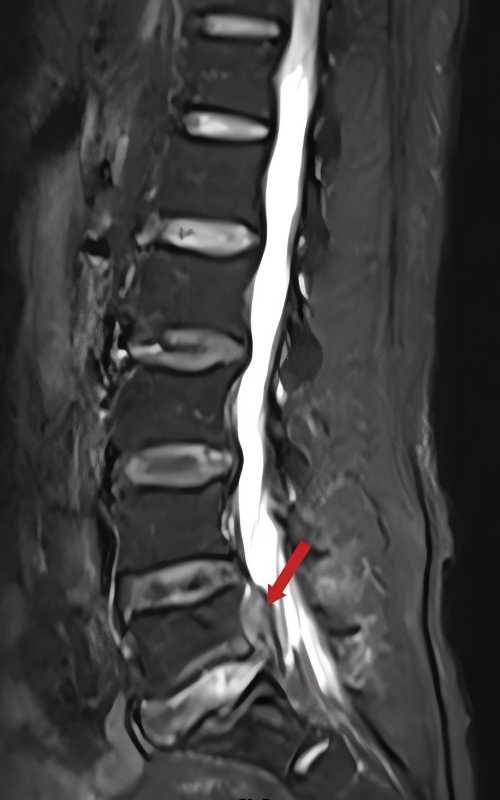

一个月前,55岁的陈先生出现腰部及右下肢疼痛,在尝试过药物、针灸等方法进行保守治疗后,症状没有得到缓解,反而逐渐加重,严重影响日常生活。经朋友介绍后,陈先生来到捷克论坛 脊柱外科沈雄杰主任医师的专家门诊求助。为患者进行详细检查后,科主任刘向阳教授、副主任沈雄杰教授等分析认为:从检查结果来看,陈先生第5腰椎及第1骶椎椎间盘巨大突出并向上方脱出,明显压迫右侧腰5神经根,并引发腰腿疼、下肢麻木等症状,属于典型的腰椎间盘突出症,已达到手术指征,需及时手术治疗。为了尽快缓解患者的痛苦,最大程度减少手术创伤,刘向阳教授和沈雄杰教授共同为其制定了手术方案,决定应用AUSS为其进行减压手术。

术前检查显示:患者腰5/骶1椎间盘突出,右侧神经根受压